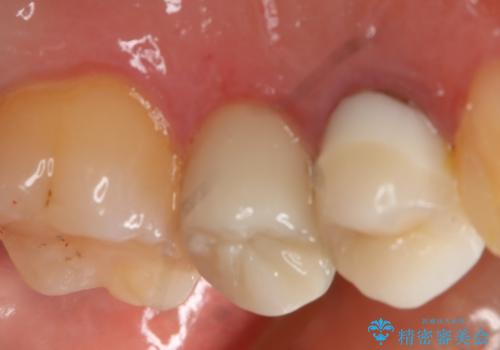

う蝕除去中に露髄 フルジルコニアクラウン

う蝕除去中に露髄したため精密根管治療へと切り替え、仮歯をはさんでセラミッククラウンを装着し終了としました。

- 99000円(フルジルコニアクラウン+仮歯)費用は治療当時の料金となります